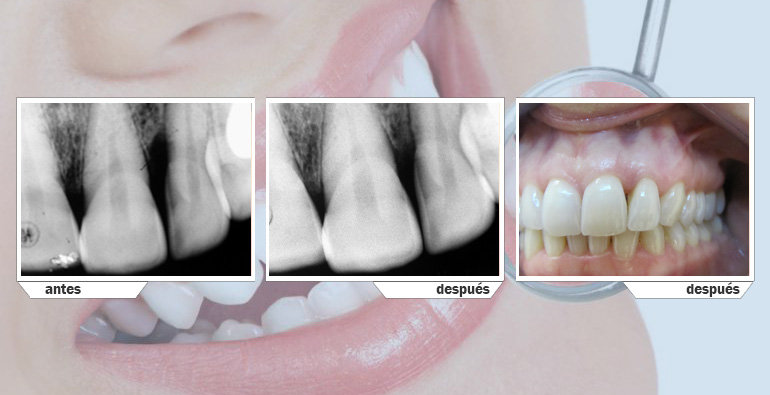

Regeneración tisular guiada.

Por medio de proteínas o barreras que evitan la migración epitelilal, con este tratamiento podemos regenerar, cemento, ligamento y hueso alrededor de dientes con defectos verticales.

En bolsas mayores a 5mm es el tratamiento ideal para evitar que la enfermedad periodontal siga avanzando.